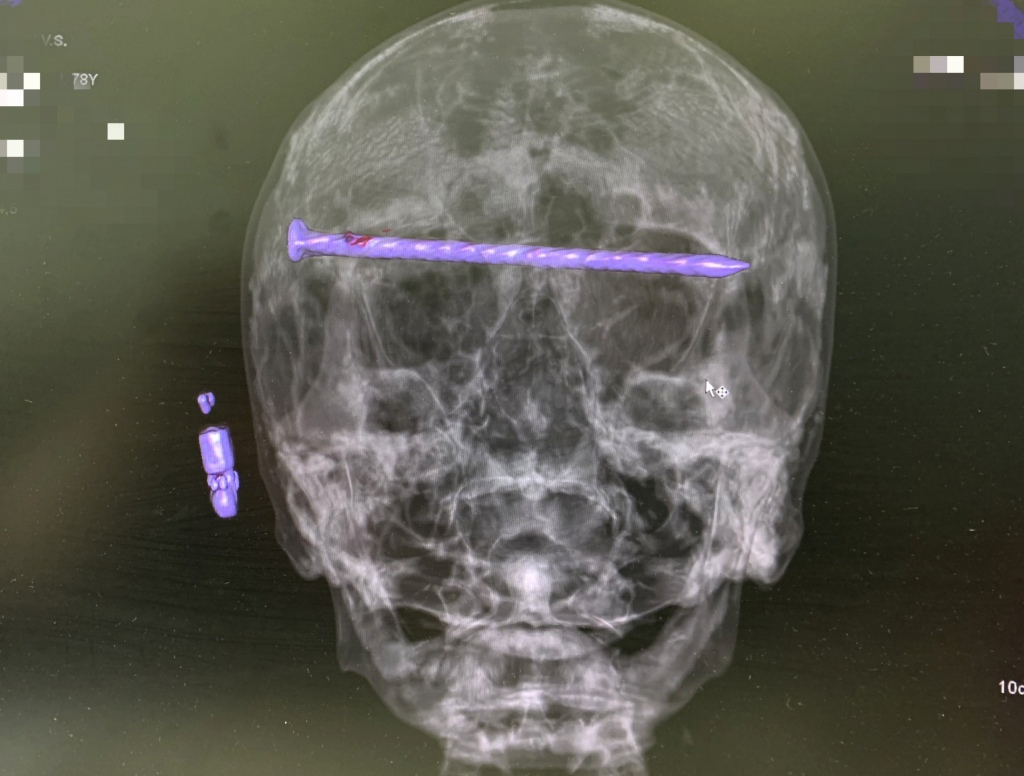

В середине июля в приёмный покой горбольницы № 1 Нижнего Тагила поступил мужчина с травмой головы в тяжёлом состоянии. В черепе пациента был 15-сантиметровый гвоздь, который прошёл через обе глазницы от правого до левого виска. Ситуация осложнялась повреждением твёрдой оболочки мозга и сдавлением глазных яблок.

Чтобы спасти жизнь пациенту, бригада врачей во главе с заведующим нейрохирургическим отделением ГБ № 1 Дмитрием Неволиным провела экстренную операцию, в результате которой мужчине извлекли гвоздь, сохранили зрение и целостность черепа. После хирургического вмешательства пенсионеру провели контрольную компьютерную томографию и перевели его в отделение. Сейчас мужчина готовится к выписке.